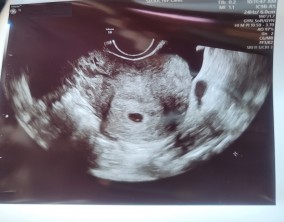

조심스러운 기쁨이 안도가 되기까지